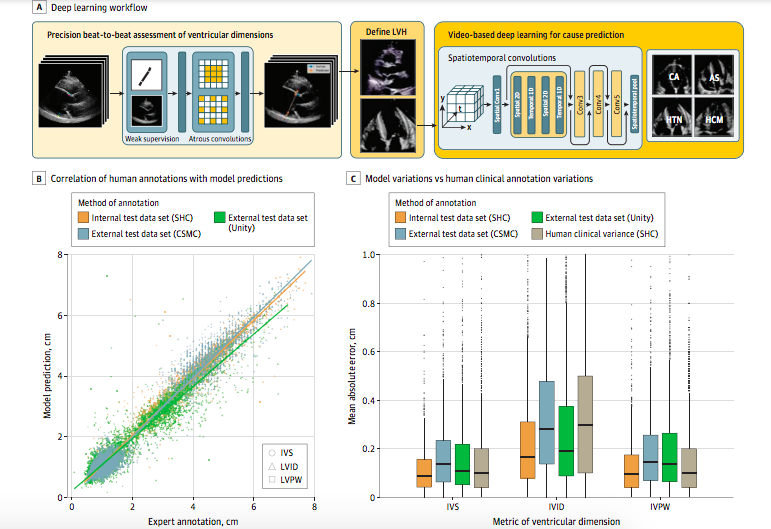

该研究所基于神经网络的深度学习,以34000多个心脏超声波视频作为数据样本支撑,通过对海量特征数据的识别和分析,获取了心脏壁厚度和心室大小相关的特定特征,从而建立起有效的AI算法模型,在读取新的图像数据时通过特征的分析比对,分辨出潜在的心脏疾病患者。微妙精细的线索,能比经验丰富的临床专家更精准地识别出高风险患者,将其与看起来非常相似的良性心脏区分开,在患者身体状况发展到可能影响健康的程度之前,及时发出预警信号,从而有效防止心脏衰竭、猝死等恶劣情况的出现。

▲AI检测心脏病原理